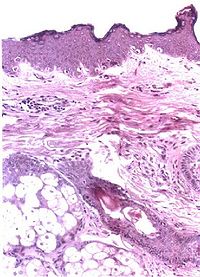

面神经炎在脑神经疾患中较为多见,这与面神经管是一狭长的骨性管道的解剖结构有关,当岩骨发育异常,面神经管可能更为狭窄,这可能是面神经炎发病的内在因素。面神经炎发病的外在原因尚未明了。有人根据其早期病理变化主要为面神经水肿髓鞘及轴空有不同程度的变性,推测可能

面神经水肿透视

因面部受冷风吹袭,面神经的营养微血管痉挛,引起局部组织缺血缺氧所致。也有的认为与病毒感染有关,但一直未分离出病毒。近年来也有认为可能是一种免疫反应。膝状神经节综合征(Ramsay-Hunt Syndrome)则系带状疱疹病毒感染,使膝状神经节及面神经发生炎症所致。